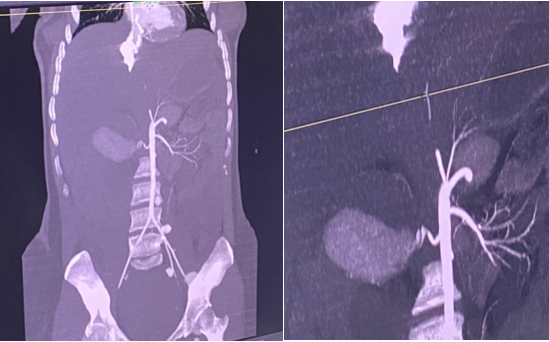

On admission to our facility, we performed an Angio scan Figure 1, which revealed a partially thrombosed aneurysm of the right renal artery, complicated by a rupture with a voluminous subhepatic hematoma; aneurysms of the inferior mesenteric artery, primitive right internal iliac artery and left internal and external iliac arteries, partially thrombosed; moderate hemoperitoneum; the patient was then transferred to the operating room. The first stage of the operation involved an unsuccessful attempt to repair the aneurysm of the right renal artery, followed by a right nephrectomy and a right hemicolectomy with stoma after discovery of ischemia of the ascending colon. The post-operative course was marked by the development of a state of haemorrhagic shock refractory to resuscitation measures, and a repeat operation was indicated but not completed following the patient's death on the table.

Figure 1 Abdomino-pelvic angioscan showing aneurysm of the right renal artery.